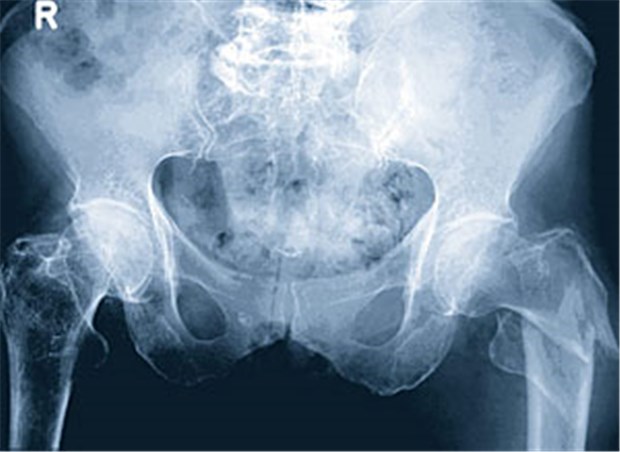

Röntgenbild Oberschenkelhalsbruch links aufgrund einer Osteoporose.

© K. Krüger, B. Manger, Merckle Rheumatol. visuell, 3. Aufl.